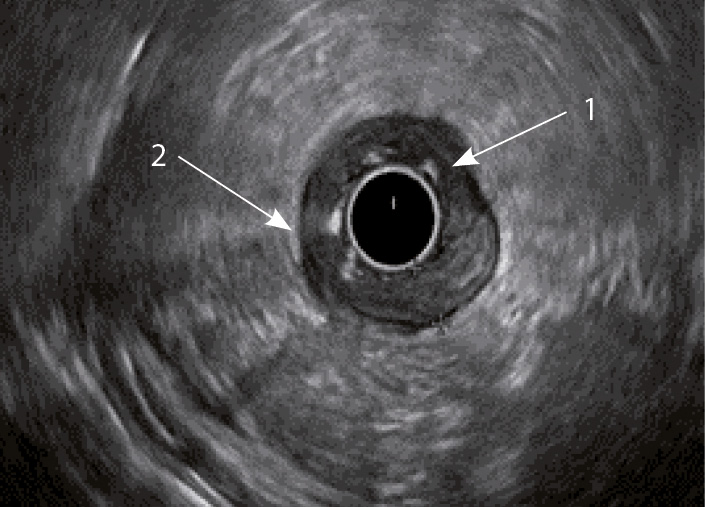

Рис. 4. Эндосонографическая картина толстой кишки при болезни Крона; 1 – отсутствие дифференцировки слоев кишечной стенки; 2 – утолщение стенки толстой кишки за счет всех слоев

Кишечная стенка статистически значимо чаще утолщалась за счет слизисто-подслизистого слоя при ЯК, чем при БК: в 82 и 7,14% соответственно; диагностическая чувствительность данного признака была 82%, а специфичность – 93% (табл. 1). При БК изменение стенки толстой кишки за счет трансмурального утолщения выявлялось статистически значимо чаще (68%), чем при ЯК (9%) (чувствительность 68%, специфичность 91%). Статистически значимых различий в частоте изменений мышечного слоя кишки отмечено не было. Только при БК в 68% случаев отсутствовала дифференцировка слоев кишечной стенки в фазе обострения (чувствительность и специфичность признака составили 68 и 100% соответственно) (см. рис. 4). При ЯК на фоне «смазанности» слизисто-подслизистого слоя у всех больных можно было визуализировать мышечный и серозный слои (см. табл. 1, рис. 3).